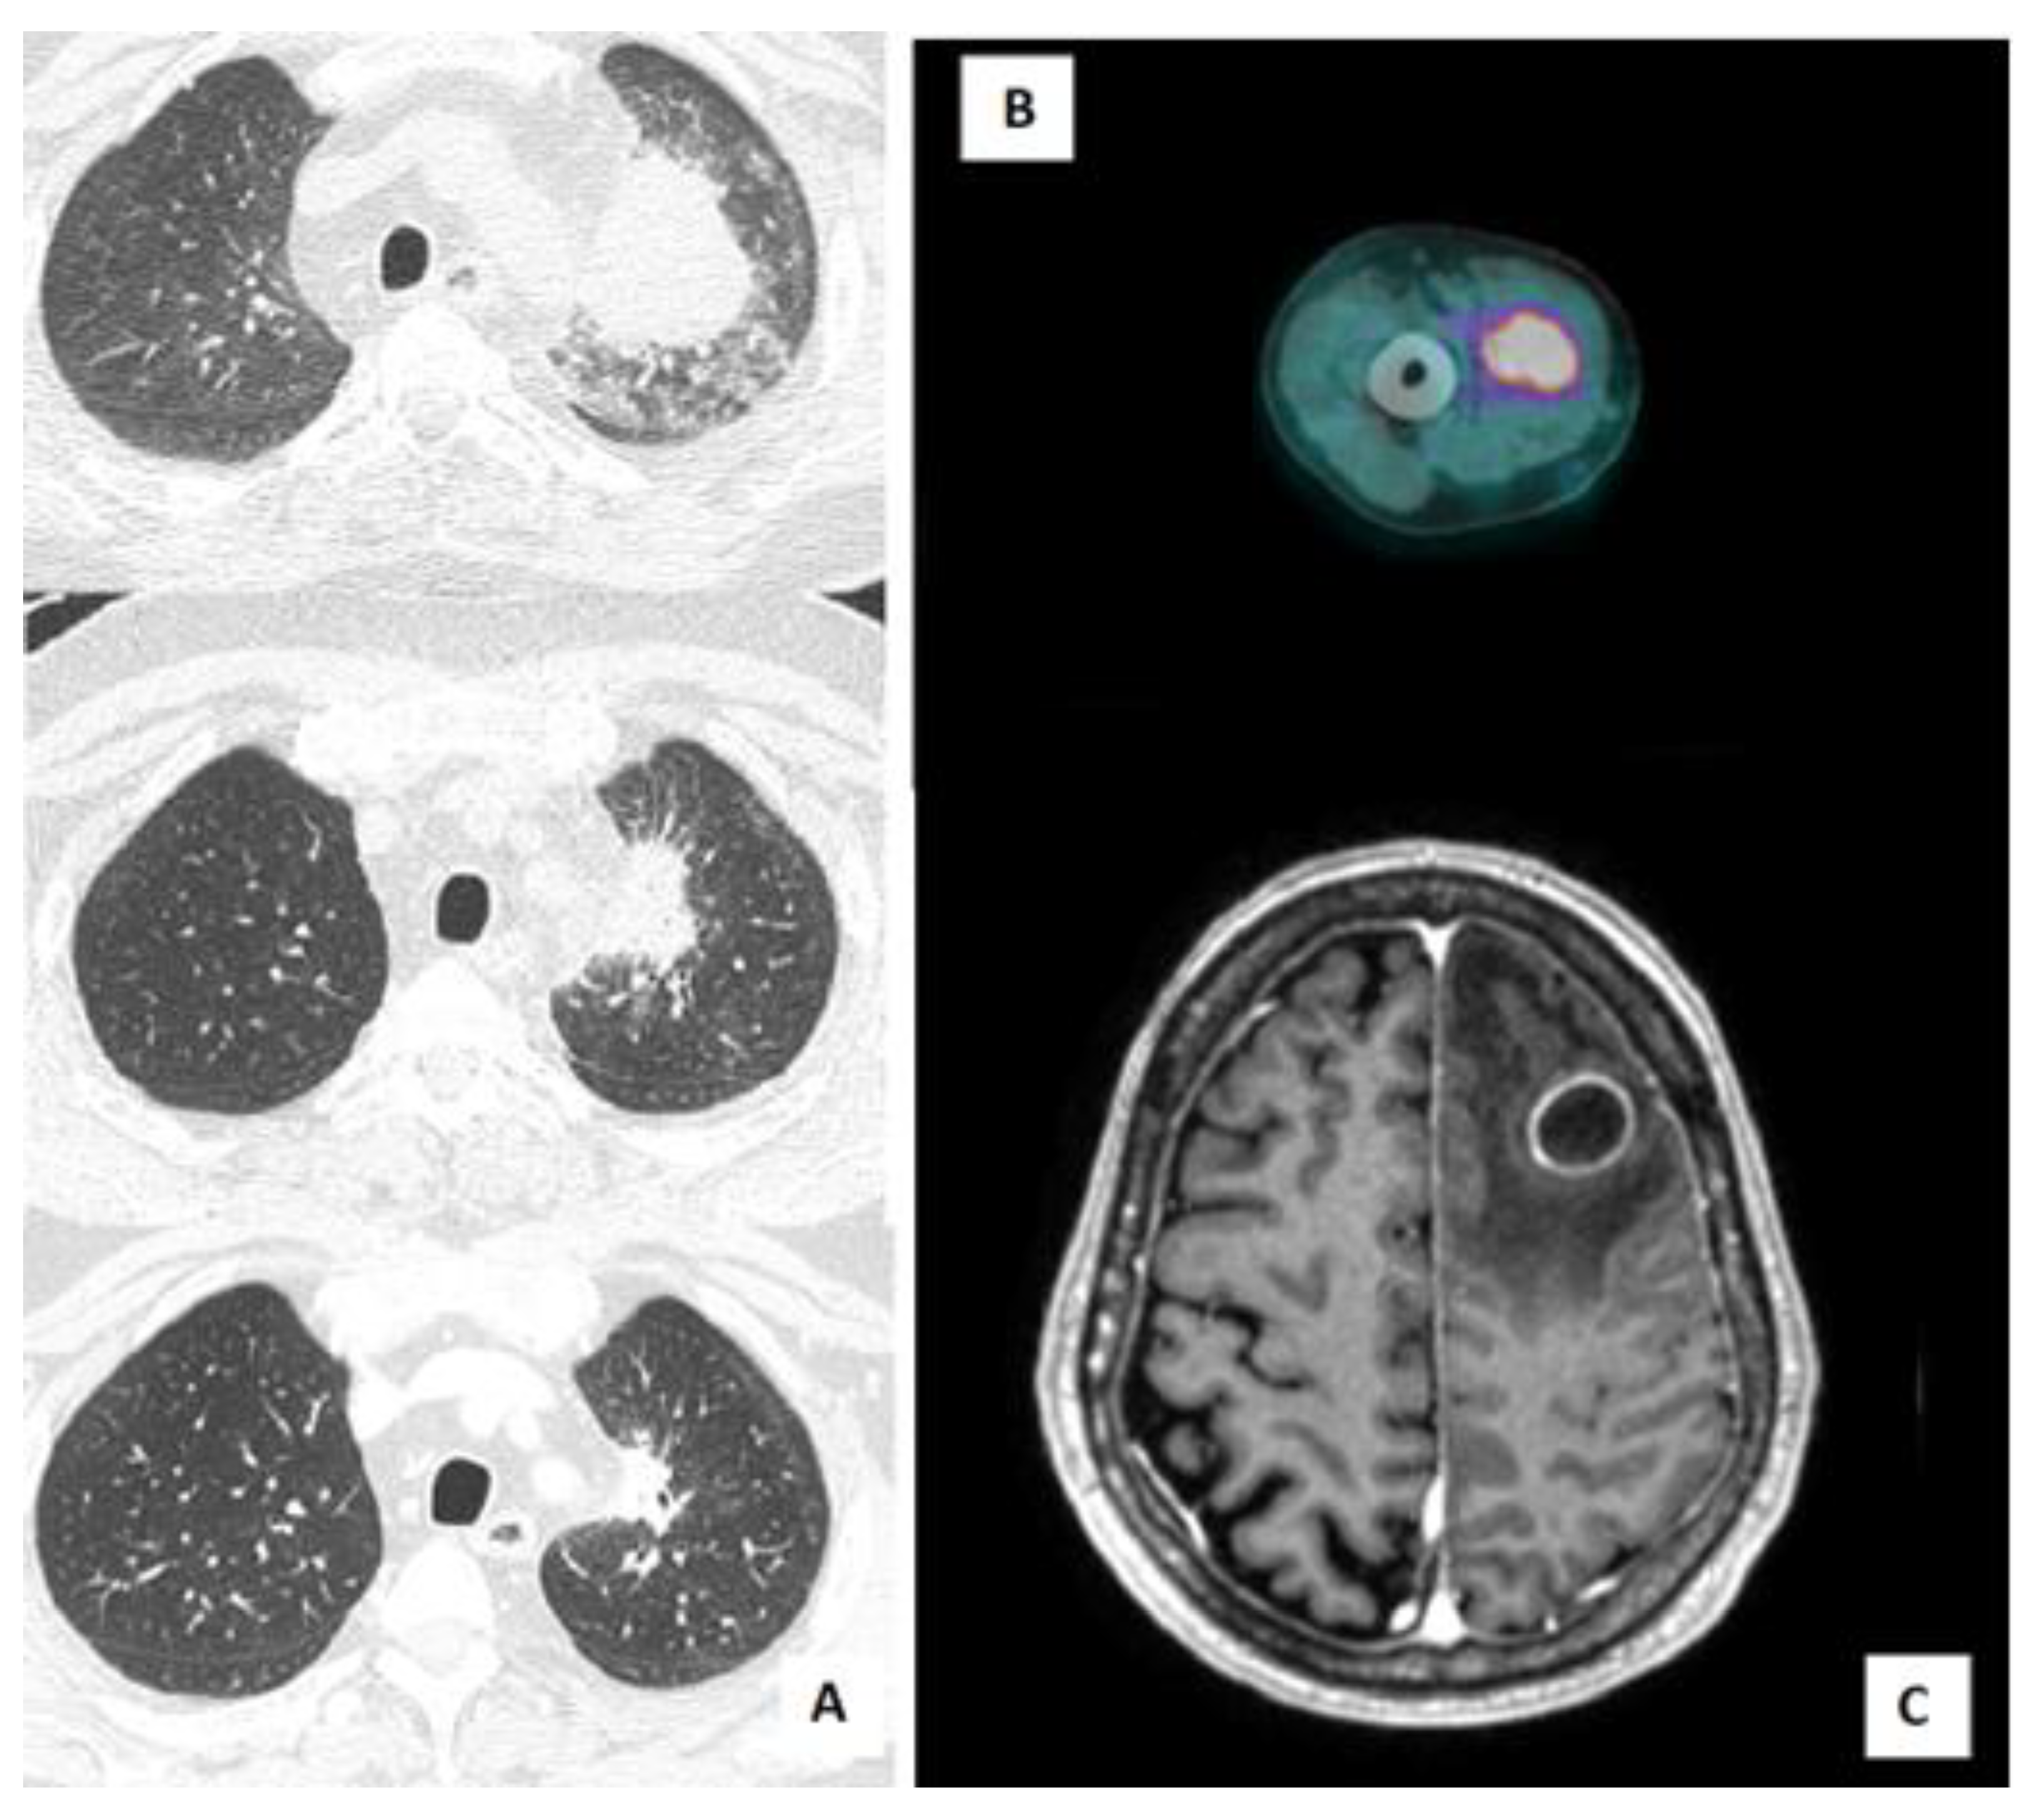

A 61-year-old man with a history of ischemic cardiomyopathy, hypertension, and bladder cancer, was diagnosed with chronic renal failure in IgA nephropathy (Berger’s disease). He started treatment with a steroid pulse regimen (also known as a “Pozzi scheme”, 1 g/day of methylprednisolone pulses for 3 consecutive days at the beginning of months 1, 3, and 5, followed by 0.5 mg/kg of oral prednisolone every other day) and, subsequently, mycophenolate as a chronic immunosuppressive therapy. The patient did not receive primary prophylaxis with trimethoprim-sulfamethoxazole (TMP/SMX). Five years after the diagnosis, he was admitted to our hospital for asthenia and decompensated diabetes. During hospitalization, a Positron Emission Tomography/Computed Tomography (PET/CT) scan was performed, showing increased fluorodeoxyglucose (FDG) uptake in a lung consolidation and in the right arm muscles (Figure 1B). A musculoskeletal ultrasound confirmed the presence of multiple hypoechogenic formations in the biceps brachii, compatible with intramuscular abscesses. Needle aspiration biopsy was performed, with isolation of Nocardia farcinica. Microbiological data became available after the patient’s discharge. The presence of cerebral abscesses was excluded by brain magnetic resonance imaging (MRI) and, because of the stable clinical conditions of the patient, antibiotic therapy with TMP/SMX (160/800 mg, two tabs every 12 h) was started with outpatient follow-up. The treatment was subsequently switched to linezolid (600 mg every 12 h) due to renal toxicity after one week. Association therapy with another drug (such as an aminoglycoside) was considered but not administered, since it was contraindicated by our consultant nephrologist. Antibiotic treatment was stopped after 5 months, given the resolution of the lesion at follow-up lung CT scan, the stable clinical conditions, and the discontinuation of immunosuppressive therapy.

An 80-year-old man with a history of Waldenstrom macroglobulinemia progressed to lymphoplasmacytic lymphoma and was placed on treatment with ibrutinib (420 mg/day) plus acyclovir primary prophylaxis. After eleven months, he was admitted to the emergency room due to progressive ideomotor impairment, disorientation, and memory deficiency. A brain CT scan and brain MRI showed necrotic lesions with associated oedema in the left frontal and parietal lobe (Figure 1C) and in the left cerebellum. A diagnostic brain biopsy was performed, with drainage of purulent material. Ibrutinib treatment was stopped, and empirical therapy was started with CEP (2 g iv every 8 h) plus vancomycin (1 g iv loading dose followed by 2 g every 24 h). Ten days later Bacillus cereus and Nocardia wallacei were isolated from a culture performed on the brain specimen. According to antibiotic susceptibility testing (AST), therapy was shifted to TMP/SMX (15 mg/kg iv divided into three doses) plus linezolid (600 mg iv every 12 h). A chest CT scan was performed, detecting multiple bilateral nodules and consolidations, along with bilateral pleural effusion. These findings were compatible with Nocardia infection. Subsequent follow-up imaging (chest CT scan and brain MRI) showed progressive improvement of the lesions. After six weeks of intravenous therapy, the antibiotic course was continued with a switch to minocycline (100 mg every 12 h) plus TMP/SMX (160/800 mg, two tabs every 12 h). The patient is still in treatment (12 months to-date) and in follow-up.

A 55-year-old man was diagnosed with Sezary syndrome (stage IV B) and started treatment with prednisone (prednisone higher than 20 mg for at least 6 months) and gemcitabine (four cycles), and then with mogamulizumab (two cycles, four and five months after the diagnosis). Prophylaxis with TMP-SMX (160/800 mg, one tab 3 times a week) was started. For disease progression, he was administered alemtuzumab (two cycles, seven and eight months after the diagnosis) and he developed cytomegalovirus (CMV) reactivation as a complication of alemtuzumab-induced lymphopenia. Nine months after diagnosis, the patient was admitted to our hospital for mild coronavirus disease 19 (COVID-19) pneumonia, treated with dexamethasone (6 mg iv for ten days) and low-flow oxygen, while he was on TMP/SMX primary prophylaxis. Ten days after discharge, he was readmitted to our hospital for fever, mild dyspnoea, and elevated inflammatory markers. A chest CT scan showed a consolidation (56 × 47 mm) in the left upper lobe. BAL was performed and empirical therapy with piperacillin/tazobactam plus voriconazole was started. Five days after collection, Nocardia abscessus was isolated from the BAL specimen. Antibiotic therapy with TMP-SMX (15 mg/kg/day iv, divided into three doses) plus ceftriaxone (2 g iv every 12 h) was started. A total-body CT scan was performed, excluding other disease localization. Prompt clinical and radiological response were achieved, with stable apyrexia and resolution of the lung lesion at a subsequent chest CT scan (Figure 1A). The patient is still in treatment (2 months to-date) and clinical follow-up.

Figure 1. Different radiological manifestations of Nocardia infection in immunocompromised hosts: (A) Chest CT scan showing the evolution of lung lesions caused by Nocardia abscessus in patient 6 during antibiotic treatment (at diagnosis, after 2 weeks, and after 4 weeks); (B) PET/CT scan showing increased FDG uptake in the right arm muscles (Nocardia farcinica intramuscular abscess diagnosed in patient 4); (C) brain MRI showing left fronto-parietal abscess by Nocardia wallacei in patient 5.